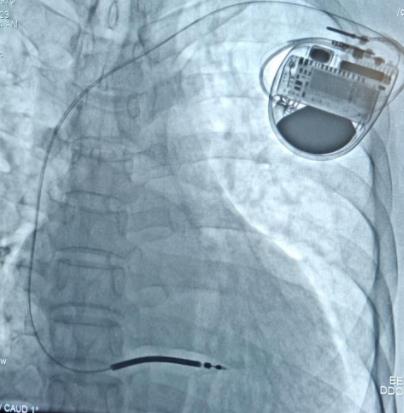

▲术后影像图

手术过程中,起搏电生理介入治疗团队依靠过硬的技术储备和丰富的操作经验,成功为刘先生进行植入型心律转复除颤器(ICD)手术,术中刘先生各项指标参数良好,血压、心率正常,手术历时1个小时,术后恢复良好,目前已办理出院。

经专家团队讨论,考虑刘先生为冠心病、陈旧性心肌梗死、心力衰竭、心脏扩大、心脏射血分数极低的患者,心源性猝死的风险高,决定为其进行植入型心律转复除颤器(ICD)手术,为生命“续航”。